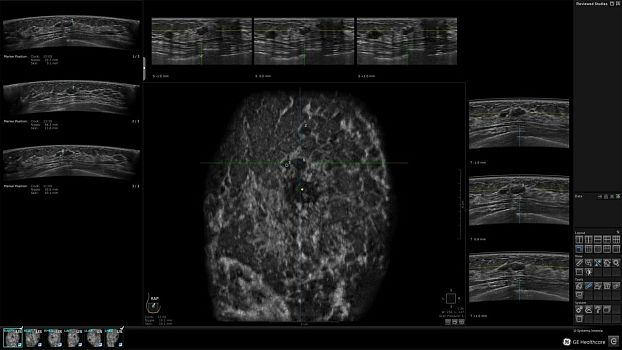

Клинические изображения

• Invenia ABUS Review Software - программное обеспечение для рабочей станци, устанавливается на рабочую станцию пользователя

• Отображение объемных 3D ультразвуковых изображений, которые состоят из традиционных поперечных и воссозданных коронарных и сагиттальных проекций

• Несколько протоколов для просмотра, которые могут быть настроены пользователем

• Многооконный просмотр: 4 - 12 изображений.

• Стандартизованная ориентация изображения:

• Изменяемая толщина среза: 0,5 - 10,0 мм (шаг 0,5 мм)

• 360 ° APC - отображение области по "любой точке компаса"